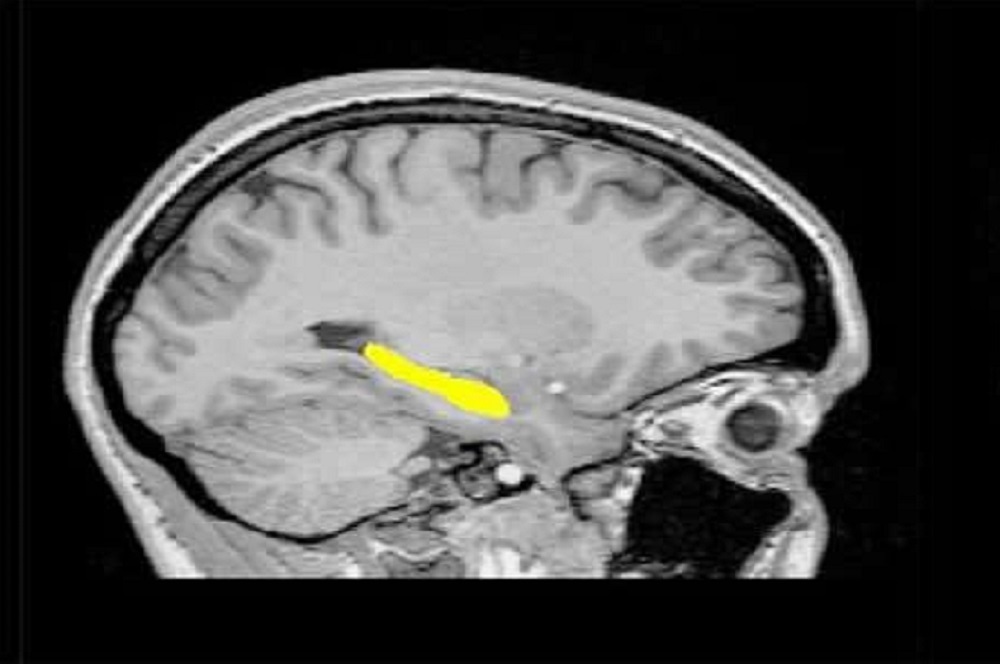

Schizophrenia is a critical, often disabling brain disorder. Symptoms can include hallucinations and delusions; dysfunctional thinking; agitated physical movements; lowered affect, and suppressed cognitive abilities such as poor focus, impaired memory or compromised executive functioning. Symptoms often emerge between the ages of 16 and 30.